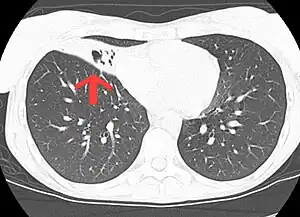

| CT scan of patient with right middle lobe aspiration and Mycobacterium avium infection consistent with Lady Windermere syndrome | |

MAC is the most commonly found form of NTM.[22] Immunodeficiency is not a requirement for MAI.[23]MAC usually affects patients with abnormal lungs or bronchi. However, Jerome Reich and Richard Johnson describe a series of six patients with MAC infection of the right middle lobe or lingula who did not have any predisposing lung disorders.[24][25]The right middle lobe and lingula of the lungs are served by bronchi that are oriented downward when a person is in the upright position. As a result, these areas of the lung may be more dependent upon vigorous voluntary expectoration (cough) for clearance of bacteria and secretions.[26][20] Since the six patients in their retrospective case series were older females, Reich and Johnson proposed that patients without a vigorous cough may develop right middle lobe or left lingular infection with MAC. They proposed this syndrome be named Lady Windermere syndrome, after the character Lady Windermere in Oscar Wilde's play Lady Windermere's Fan. However, little research has confirmed this speculative cause.[27][24]